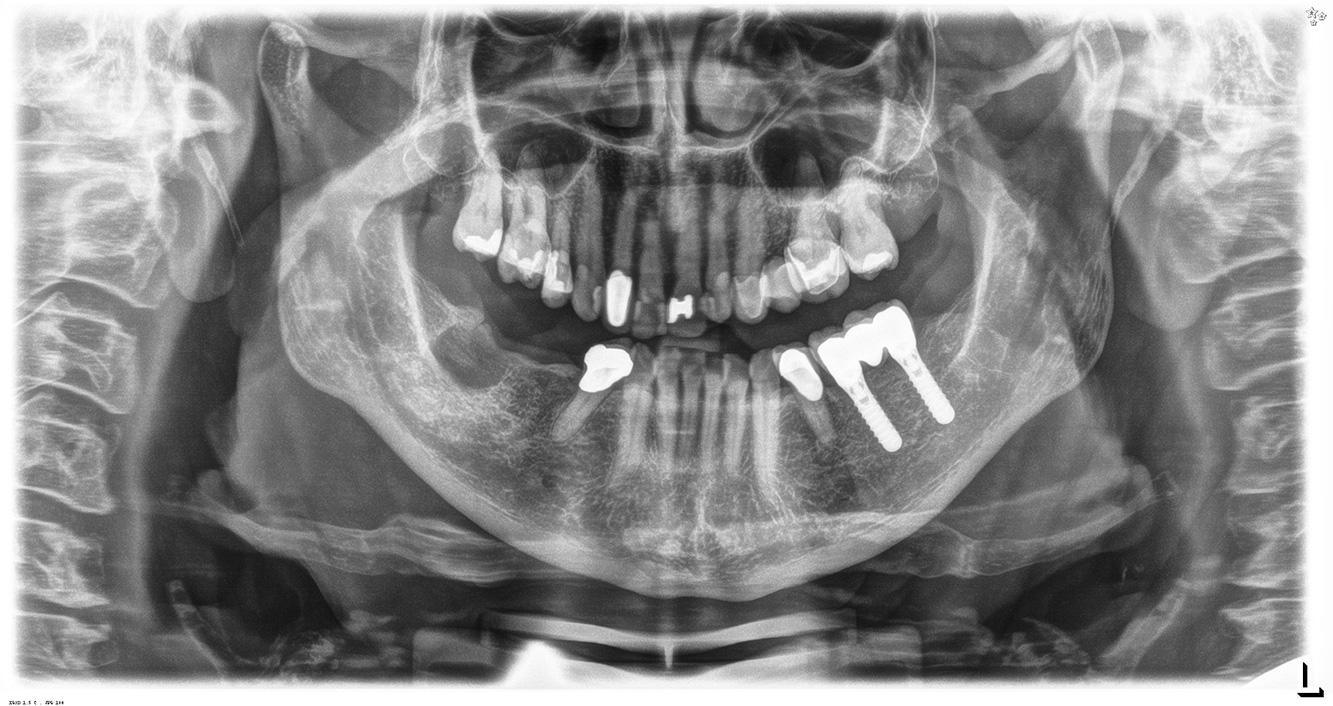

In the medical history, the 55-year-old patient states that he has no systemic disease and is not taking any medication. The patient’s lifestyle is similarly unremarkable. The patient has a few tooth restorations and two implants (2nd and 4th quadrants). On the basis of current findings, gingivitis is identified in an otherwise stable periodontal condition on the reduced periodontium (stage III, grade A). more

The healthy patient with pre-existing periodontal disease & peri-implantitis

The 68-year-old patient has no general health conditions and is not taking any medication that may be relevant to her oral health, and her lifestyle does not pose any particular risk. The patient has two dental implants (3rd quadrant, for five years) and a previous case of periodontal disease (stage IV, grade B periodontitis) with tooth loss. Currently the periodontal conditions are stable. However, periodontitis significantly increases the biological complications of implantations and there is a risk of implant loss (21). Four recommendations can be determined for the prophylaxis session. more